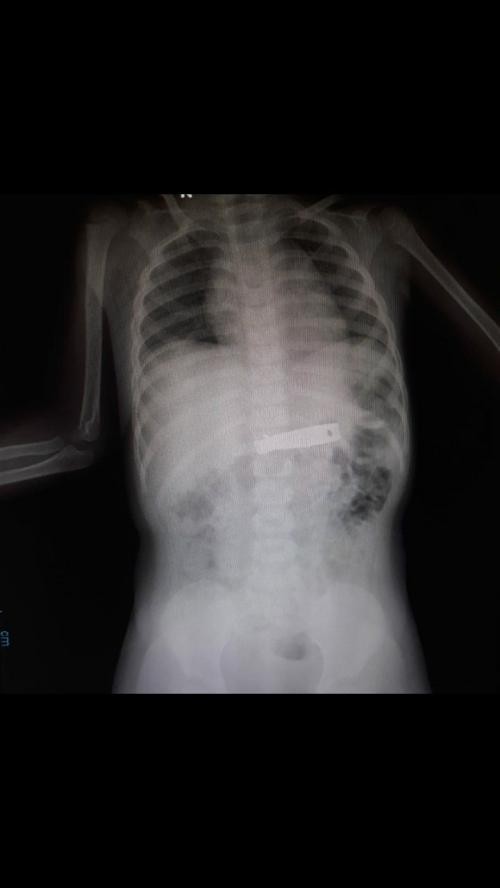

Simak Kisaran Biaya Rontgen Tulang Belakang. (Foto: MNC Media)